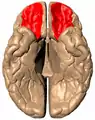

![]() Orbital surface of left frontal lobe. | |

Orbital gyrus shown in red.

Basal surface of cerebrum. Orbital gyrus shown in red.